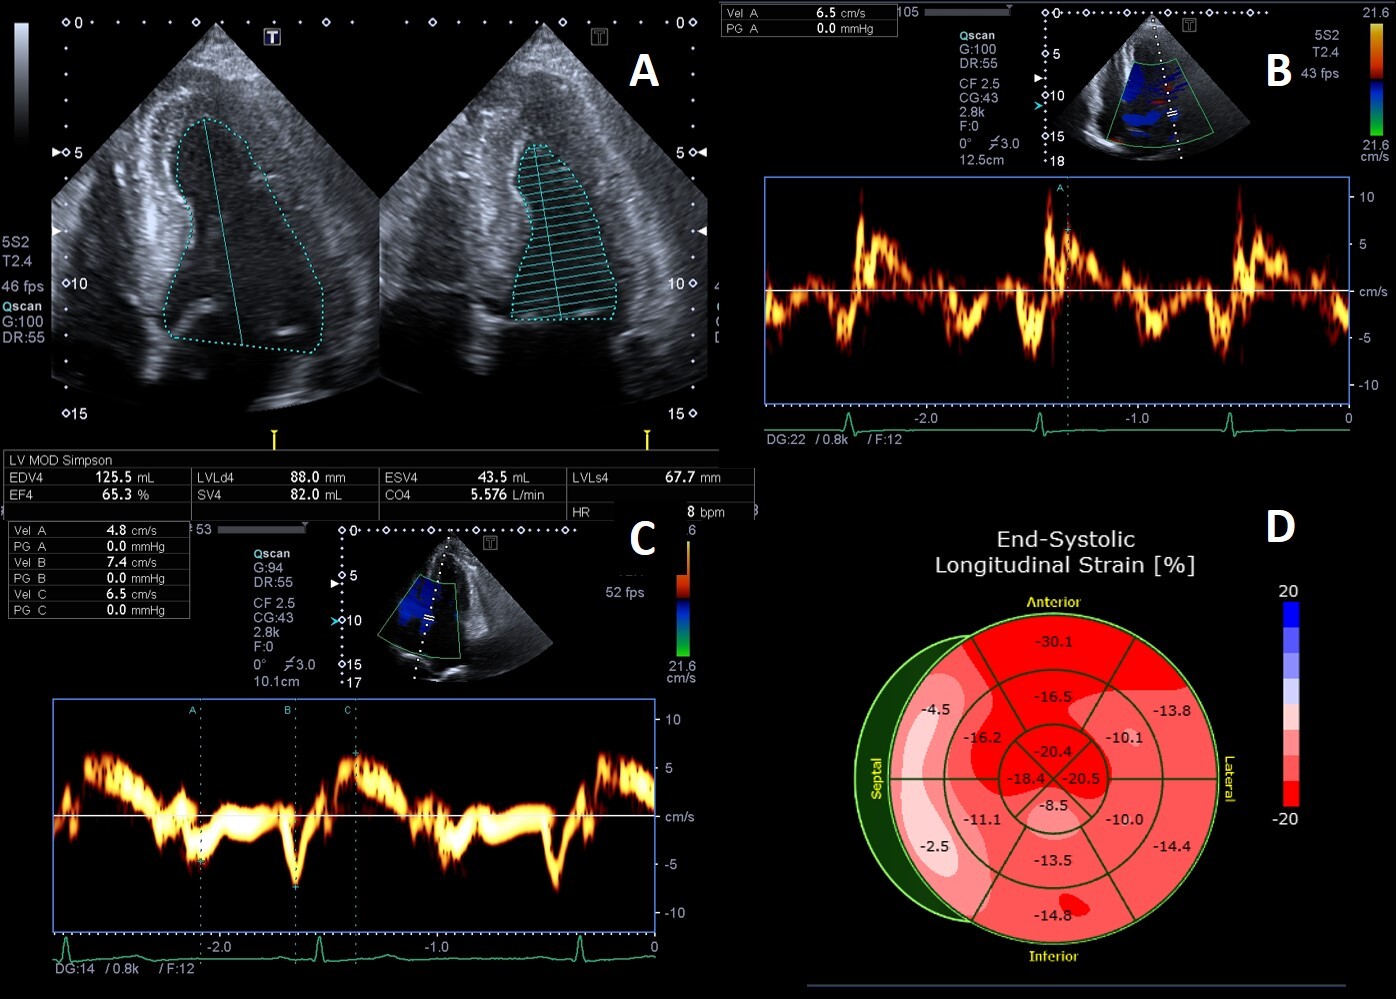

Deposition of glycolipids has been histologically reported in all four heart valves [74]. Leaflet thickening and redundancy are commonly encountered (Fig. 4), affecting the mitral and aortic valves in up to 57% and 47% of patients, respectively [15].

Fig. 4.Example of valvular heart involvement in Fabry Cardiomyopathy. (A, B) Parasternal long-axis and short-axis views showing thickened mitral valve leaflets (arrows). (C) Color Doppler four chamber view focused on the mitral valve, the green line represents the vena contracta width (4.3 mm) suggestive of moderate mitral regurgitation. (D) CW Doppler across the mitral valve.

Mild mitral and aortic regurgitation are frequently detected on echocardiography, while moderate or greater valvular regurgitation is rare and infrequently lead to clinically significant outcomes. Mitral valve prolapse was described as a frequent finding in the past [75] but this was not confirmed recently [76], likely due to implementation of stricter diagnostic criteria [9]. We recently described a case of isolated chordal rupture, which occurred without valve leaflet prolapse, in a patient with Fabry cardiomyopathy. We speculated that in this case chordal rupture could be due to sub-valvular apparatus storage of glycosphingolipids rather than fibro-elastic deficiency [77]. Valvular stenosis is rarely described, even if a case of rapidly progressive aortic stenosis has been reported, and the author proposed that it could have been caused by severe calcification of the aortic valve, as a consequence of valve thickening due to FD or both processes that finally potentiated each other [78].

However, in the largest cross-sectional study conducted so far on 714 patients from 11 countries, only 14.6% had clinically relevant heart valvular disease, and just three patients in the entire cohort had specific indication for valve surgery [5], unlike other storage diseases [79].